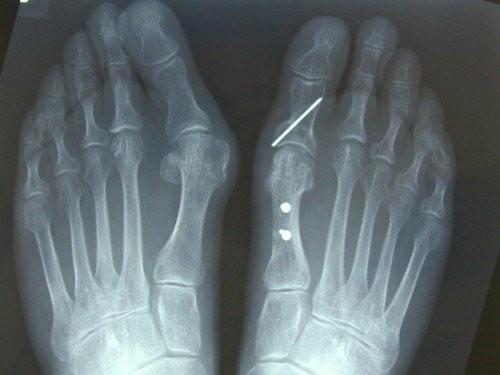

x线片通过观察第一跖骨和近节趾骨的中轴线之间形成的角度来确定拇外翻的存在。如果角度大于15度,则诊断为拇外翻。45-50°的角度被认为是严重的。同时还应考虑第一节MTP关节内的籽骨移位程度和骨关节炎程度的变化。

如果非手术治疗失败,可以考虑手术治疗。(证据级别:4)在选择手术前,必须确定拇外翻的严重程度。为了做到这一点,使用了负重平片射线照相术。

这种手术通常用于轻度畸形。截骨术呈“V”形。然后将松动的截骨以不同的方式放置,以纠正第一跖骨角度。截骨块用克氏针或螺钉固定。

从第一跖骨头的头部取出楔子,以便更好地组织关节软骨。楔块位于背侧和内侧基部。在某些情况下,外科医生认为旋转关节软骨是必要的。用螺钉或K线固定。